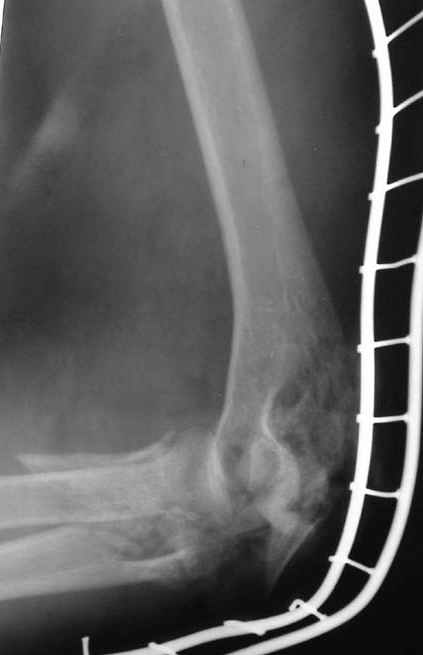

Уважаемые коллеги! Мужчина, 30 лет. В состоянии алкогольного опьянения заснул на рельсах и, по собственным словами, <слегка зацепился за трамвай>.

Обширная почти циркулярная (3/4 рана), в которую выстоят осколки костей с фрагментами суставной поверхности. Обширные ушибы и размозжения мягких тканей вокруг раны. Пульсация на лучевой артерии удовлетворительная, на локтевой слегка ослабленная. Снижение чувствительности в пальцах.Предложения по тактике лечения? Заранее благодарю!!! С уважением,А.В.ВладзимирскийДонецкий НИИ травматологии и ортопедииДонецк, Украина